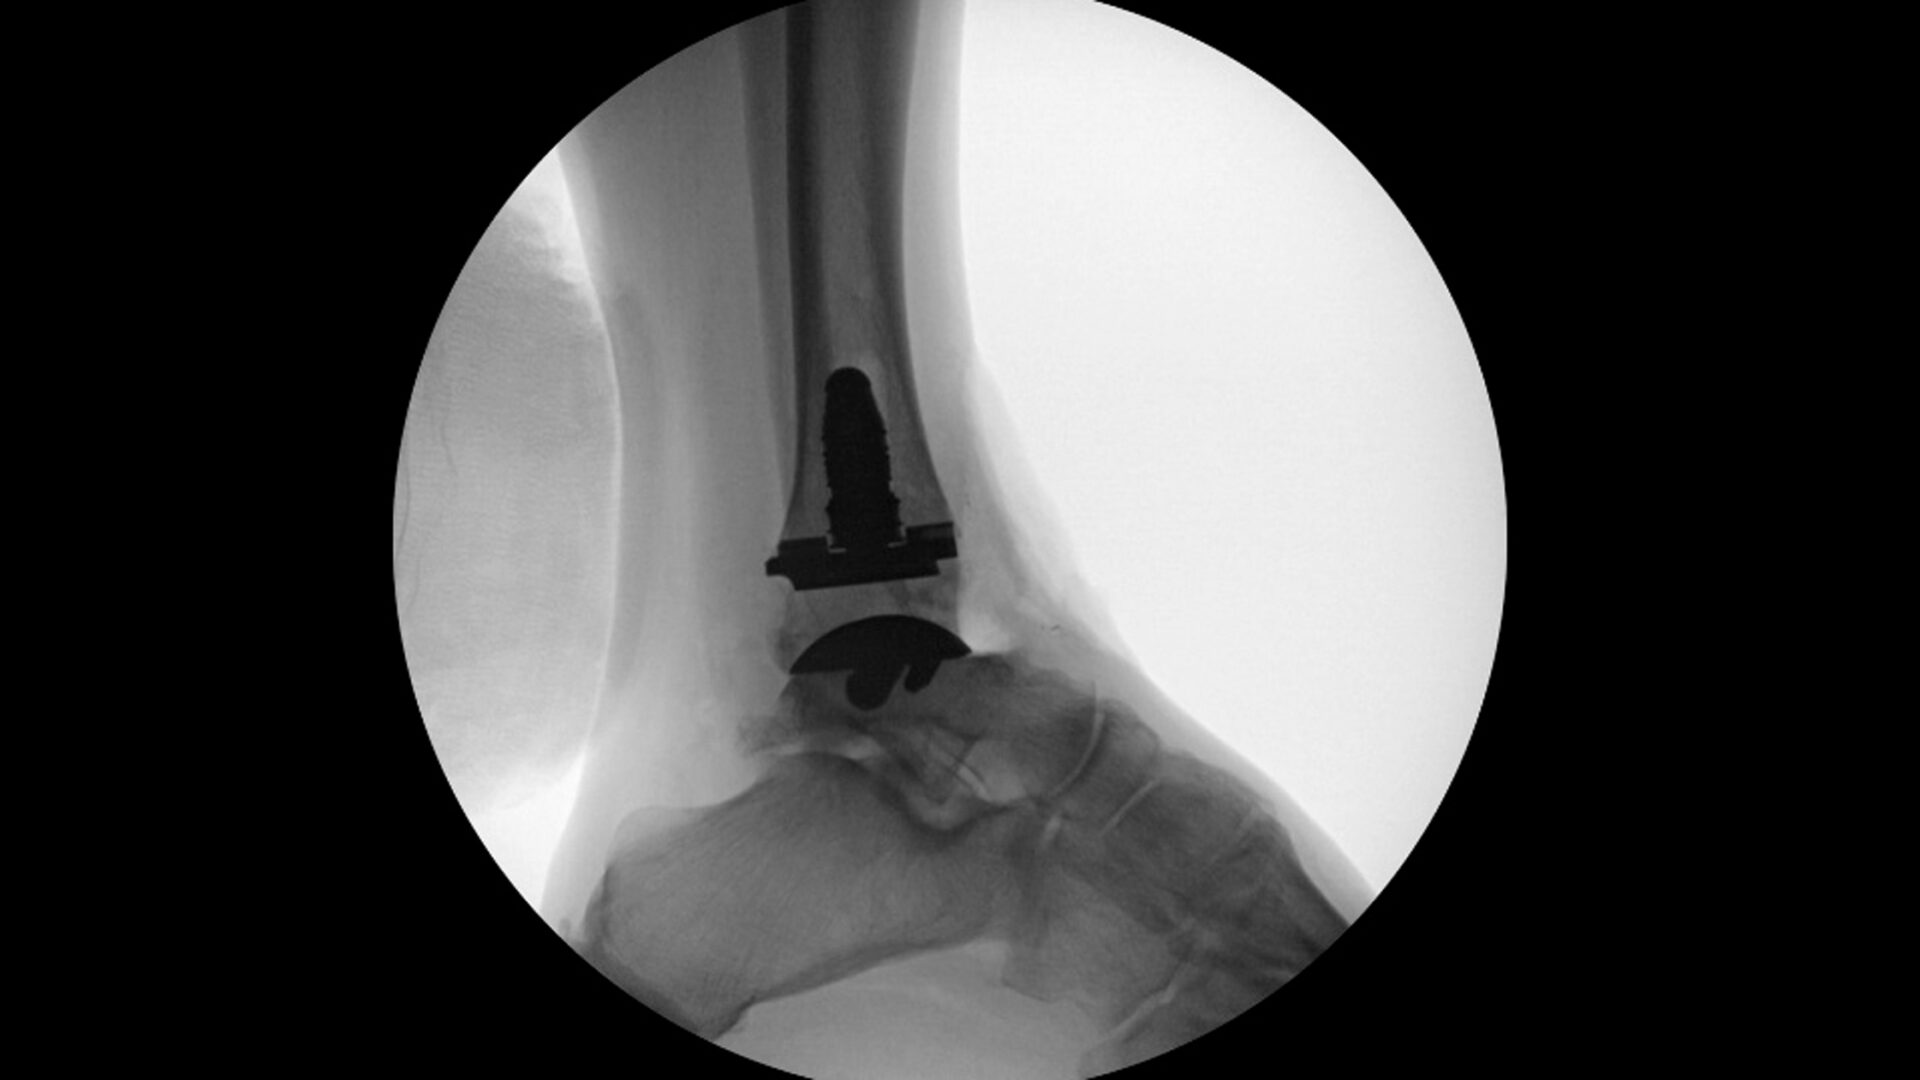

A 57-year-old patient presented with longstanding ankle pain refractory to conservative treatment. Prior nanoscopic debridement with platelet rich plasma injection provided only six months of relief. Imaging demonstrated significant joint space narrowing, subchondral sclerosis, exostoses at the talar neck, subtalar joint, talar gutters, as well as a cavovarus hindfoot alignment consistent with end-stage ankle arthritis.

The team proceeded with total ankle arthroplasty with patient specific instrumentation (PSI). After placement of the PSI, intraoperative varus tilting revealed the need for a concomitant lateral ankle ligament reconstruction. The forefoot-driven cavovarus hindfoot deformity was corrected with a first metatarsal dorsiflexion osteotomy.